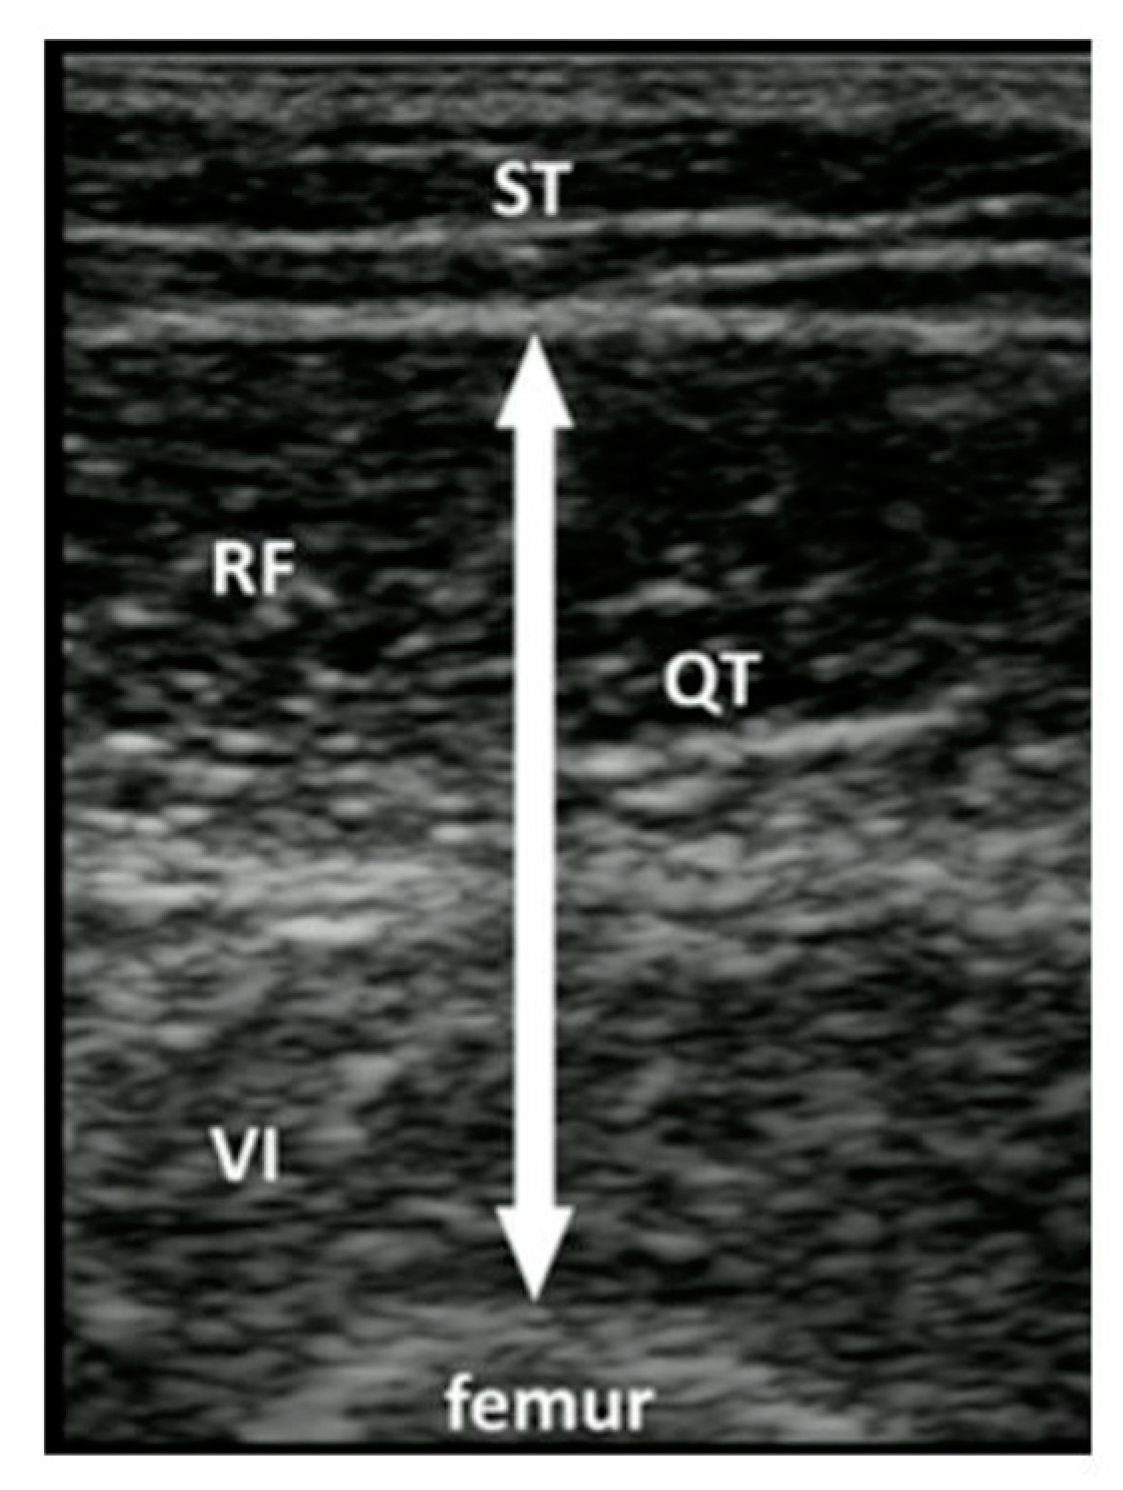

Figure 2.

Ref. [33] Thigh muscle thickness measurement. ST = subcutaneous tissue; RF = rectus femoris; VI = vastus intermedius; QT; quadricep’s thickness.

RAs asked participants about their history of falls and fall-risk factors and then measured the thickness of upper and lower limb muscles using POCUS as well as measured grip strength, and they asked the patients’ cooperation to do the Timed up and go (TUG) test. We used the standard POCUS ultrasound machines (Mindray, TE7, 2019) and linear transducer with a frequency range of 2–8 MHz available in the ED to measure the muscle thickness of each patient’s upper and lower extremities on their dominant side. Following Perkisas, the biceps landmark was the midpoint between the acromion process and the elbow crease at the anatomical position [29,40]. The thigh muscle (rectus femoris/vastus intermedius) landmark was the midpoint between the anterior superior iliac spine and the proximal patella at the anatomical position [41,42]. Participants were instructed to lie down on the couch with their hips and knees extended against the couch. A copious amount of water-soluble gel was applied to the skin to avoid pressure on the muscle. The RA measured the muscle by including the muscle belly and fascia and excluding subcutaneous adipose tissue or skin and stored the images in the protected hospital cloud data storage system.